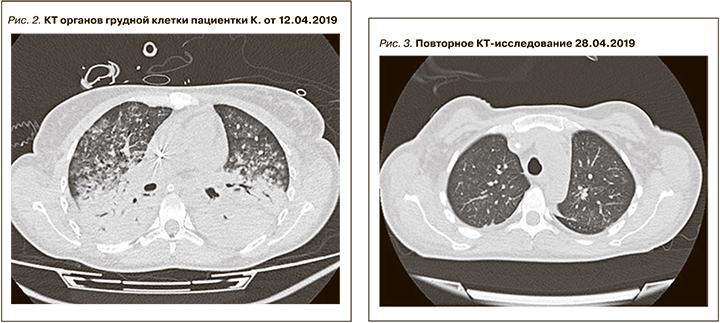

В отделение реанимации ГКБ 52 поступила 10.04.2019. При поступлении состояние крайне тяжелое, уровень сознания – медикаментозная седация (пропофол), 5–6 по Ramsey, SOFA 10 баллов.

ИВЛ проводили через трахеостомическую трубку в режиме VCV: ДО 475 vл, ЧД – 14 в минуту, FiO2 40%, SpO2 96%. Аускультативно выслушивается жесткое дыхание, ослабленное над всеми отделами легких, хрипы отчетливо не выслушиваются. При санации небольшое количество слизисто-геморрагического отделяемого. По данным из представленных документов ГКБ им. С.С. Юдина ДЗМ известно, что 09.04.2019 проведено исследование органов грудной клетки (рис. 1).

Заключение: КТ-картина обширного острого альвеолярного повреждения легких (наиболее вероятно – легочные кровоизлияния) с признаками начальной резорбции геморрагий, малое количество патологического пристеночного субстрата в трахее и главных бронхах. При пересмотре КТ от 09.04.2019 выявлен вдавленный перелом рукоятки грудины.

Лабораторные исследования: гемоглобин – 91 г/л, гематокрит – 25,3%, тромбоциты – 75 тыс/мкл, лейкоциты – 9,5 тыс/мл, общий белок – 46,6 г/л, альбумин – 27,3 г/л, мочевина – 20,3 ммоль/л, креатинин– 316 мкмоль/л, билирубин – 19,2 мкмоль/л, АСТ – 8,3 ЕД/л, АЛТ – 7,4 ЕД/л, ГГТ– 60,4 ЕД/л, ЩФ – 124 ЕД/л, ЛДГ – 811 ЕД/л, амилаза – 9,3 ЕД/л, холестерин – 3,07 ммоль/л, рН – 7,389, рО2 – 155 мм рт.ст., ИО – 390; КФК – 214,7 ЕД/л, триглицериды – 4,04 ммоль/л, ЛПВП – 0,45 ммоль/л, ЛПНП – 1,79 ммоль/л, С-реактивный белок (СРБ) – 90,89 мг/л. АНФ – 6,7, АТ к МПО – 66,5 (N 0–20), С3 – 42 (N 90–170), С4 – 8 (N 10–40).